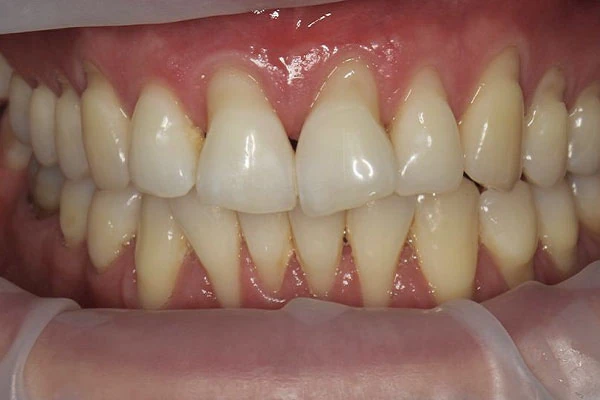

- рецессии (оголение корня зуба)

- неровный, несимметричный десневой контур (десна на разных зубах находится на разных уровнях)